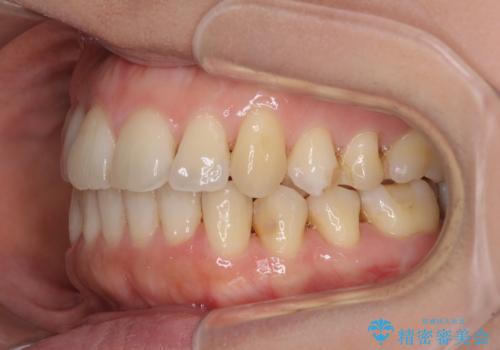

- 上下奥歯の欠損を気にして来院された患者様です。

以前矯正した後戻りにより前歯に叢生が認められたため、矯正治療の提案をしたところ、補綴治療と合わせて矯正治療を行うこととしました。

後戻りの程度は軽度であったため、インビザライン・ライトを用いて歯列を整えました。